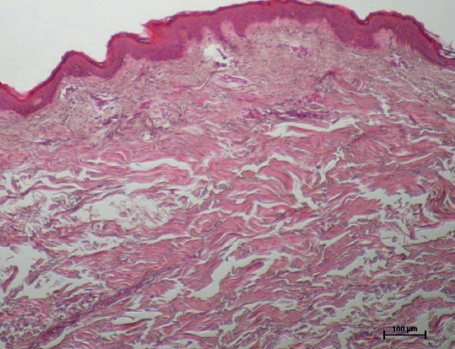

실제 온다 리프팅 시술 후 피부 진피의 콜라겐 변화를 확인한 조직학 사진입니다.

시술 전과 후를 비교해보면 콜라겐 생성을 통해 훨씬 치밀해진 피부층을 확인할 수 있죠.